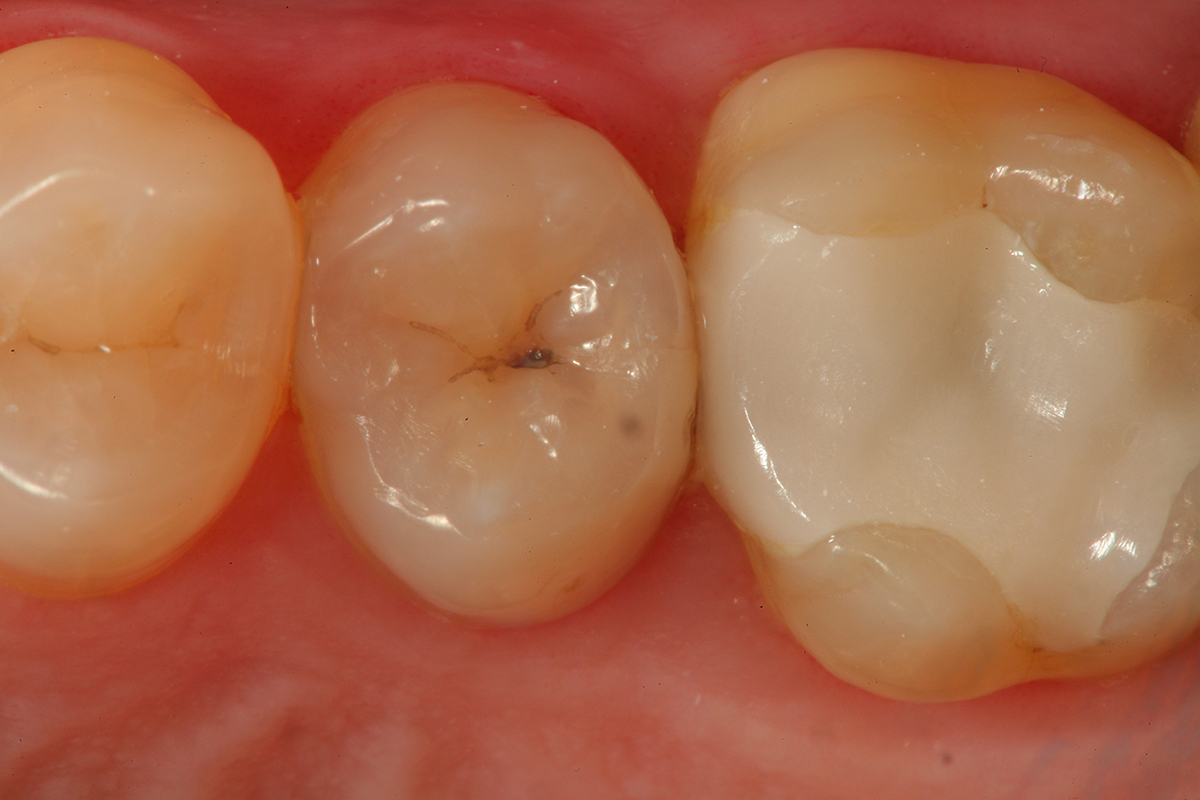

Fig 9. A preoperative occlusal view of teeth Nos. 18 and 19 with composite restorations that are exhibiting marginal breakdown.

Figure 9